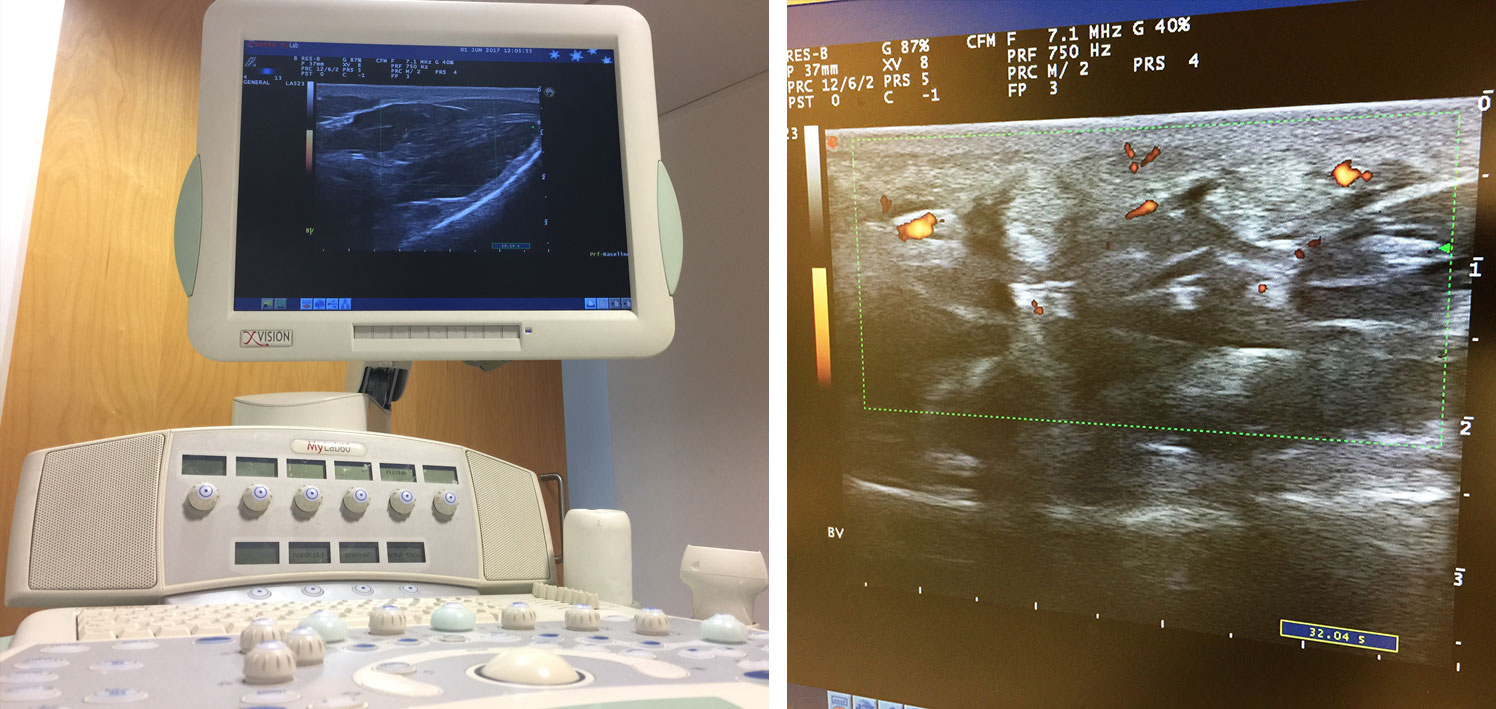

Ecografia articular y muscular

< Volver a "Pruebas diagnósticas"La Ecografía del Aparato Locomotor es una prueba complementaria esencial en el abordaje del dolor y nos permite visualizar tendones, músculos y articulaciones en directo sin dañar ni irradiar al paciente. Nos permite ver al instante el interior de las estructuras y poder diagnosticar con precisión el alcance y la gravedad de la inflamación.

En la actualidad es considerada como una prolongación de la exploración física y es fundamental en la asistencia clínica diaria del reumatólogo. Otra aplicación esencial es la ecografía intervencionista, que permite guiar las punciones diagnósticas y/o terapéuticas alcanzando la máxima precisión. Disponemos de un ecógrafo de alta resolución en HD: ESAOTE® Mylab 60.